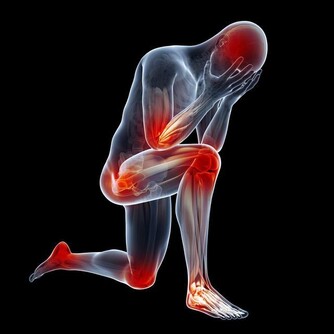

尤其是老年人,午睡時間超過90分鐘,就會增加心腦血管疾病的發生率。對於沒有午睡習慣的人,以白天自我感受的清晰度為主,只要不覺得困倦、疲勞,完全可以不需要午睡。

工作一個上午後,午睡15~30分鐘,就能讓人從疲勞中恢復過來。但是如果午睡的時間超過了30分鐘,就處在不宜喚醒的深睡期,醒來之後容易返款,還會打亂身體的生物鐘,影響晚上的睡眠的質量。